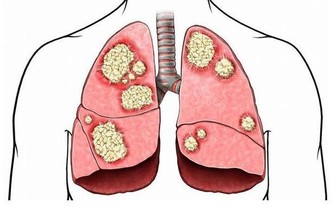

黃斑:缺乏維他命E,也可能是淋巴系統、呼吸系統有問題。